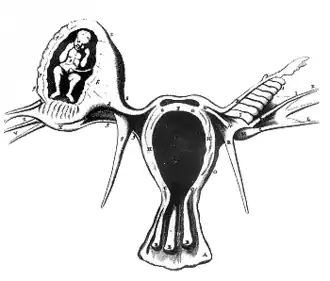

Neuf dixièmes des grossesses extra-utérines ont lieu au niveau d'une trompe de Fallope[2], reliant l'ovaire à l'utérus. On parle alors de grossesse tubaire. Les rares cas de grossesses extra-tubaires sont de diagnostic plus difficile, entraînant un taux de complications plus important.

Les formes non tubaires sont rares. La localisation ampullaire est la plus fréquente. Elle est parfois de révélation tardive, pouvant réaliser un avortement tubo-abdominal.

La localisation peut être ovarienne, isthmique (de révélation précoce), interstitielle (avec rupture au niveau de la corne utérine), abdominale (avec implantation sur n’importe quel organe) ou rétro-utérin.